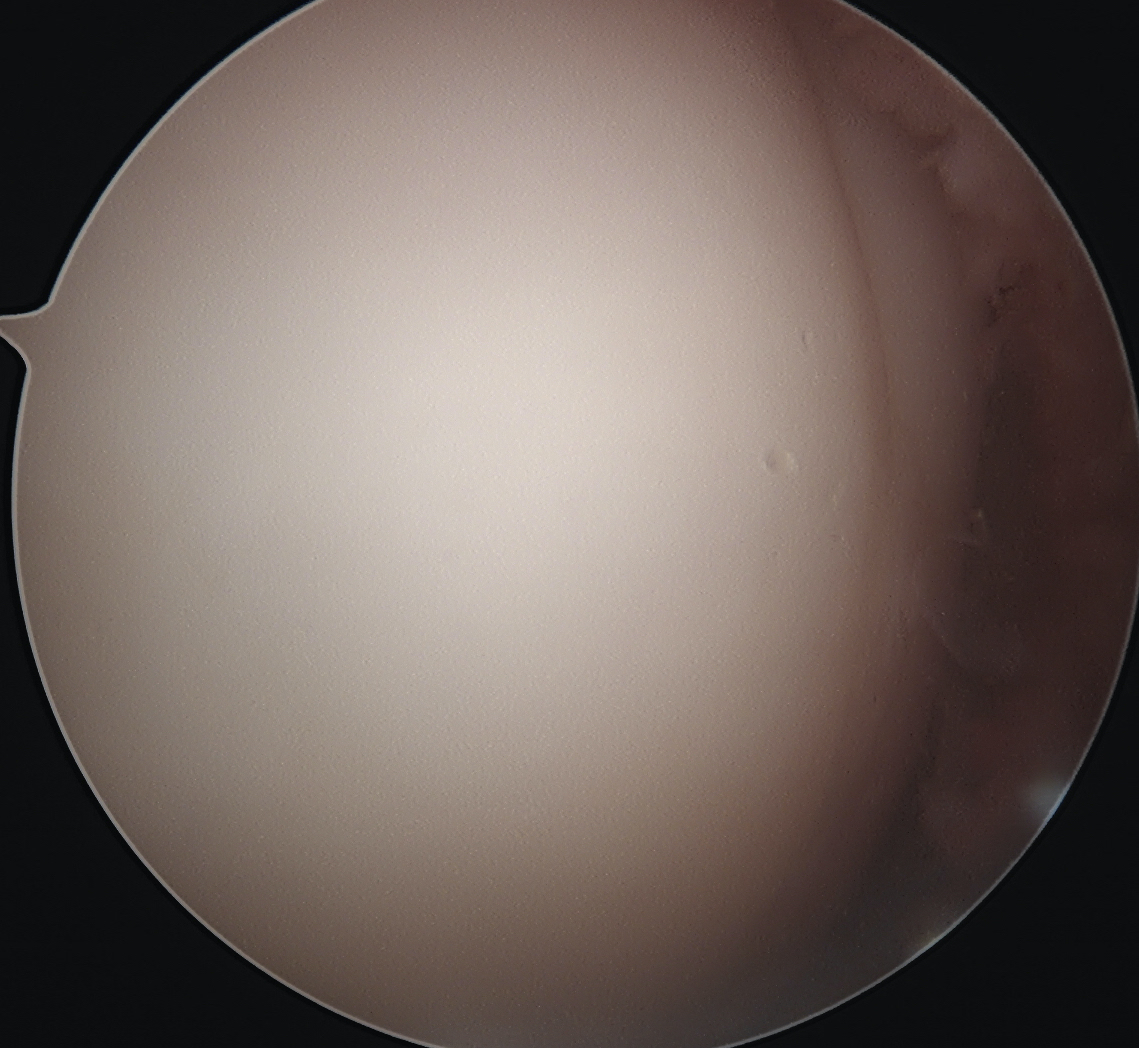

Arthroscope in lateral portal

Clear fat pad

Ensure can see entire dimensions of OCD

If fragment is displaced, reduce and pin with accessory K wire